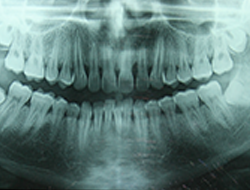

OPG-PIC

OPG

An OPG is a Panoramic or wide view x-ray of the lower face, which displays all the teeth of the upper & lower jaw on a single film.